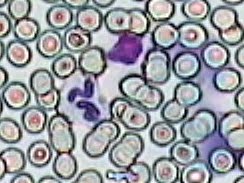

Imágenes tomadas de las preparaciones de los alumnos de 3º ESO sobre un frotis sanguíneo

244x183 píxeles